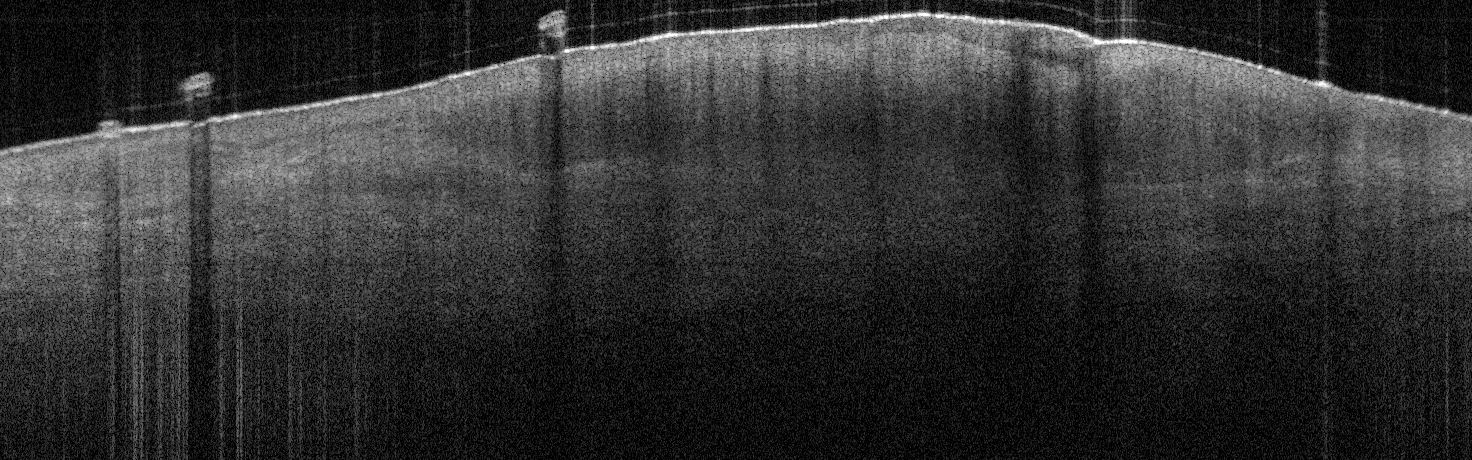

VA1: Left Forearm, Actinic Keratosis

VA1: Right Forearm, Normal